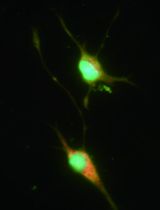

To determine humoral alloimmunity, de novo alloantibodies production is induced in one-way MLR. Amount and capacity of generated alloantibodies in the supernatant of each one-way MLR are assessed using an antibody-mediated cell dependent cytotoxicity (CDC) assay. The principle of the assay relies on the assessment of cellular survival of resting PBMCs isolated from the same donors, supplemented with the alloantibodies from the one-way MLR supernatant (Figure 1). Cell survival was measured by performing a well-known cell proliferation assay [Tetrazolium salt 2,3-bis-(2-methoxy-4-nitro-5-sulfophenyl)-2H-tetrazolium-5-carboxanilide, XTT cell proliferation assay kit].

Figure 1. Assessment of humoral alloimmunity in mixed-lymphocyte reaction. The flow-chart depicts the protocol to assess humoral alloimmunity using MLR. In one-way MLR, responder PBMCs produce alloantibodies against the mitomycin-C treated stimulator cells. Blood A and B correspond to blood donors A and B, respectively. Blood B sample will be used to generate the resting cells of that donor that will constitute the responder cells against the mitomycin-C treated stimulator cells of Blood A. Resting cells, or responder cells of Blood A will be used against the mitomycin-C treated stimulator cells of another blood donor’s sample (e.g., Blood B). Quantitative measurement of alloantibodies in the supernatant of the MLR is assessed by adding this supernatant to resting PBMCs (from the same individual who provided the stimulator PMBCs used for the MLR) using an antibody-mediated CDC assay and measuring cell viability with XTT assay.